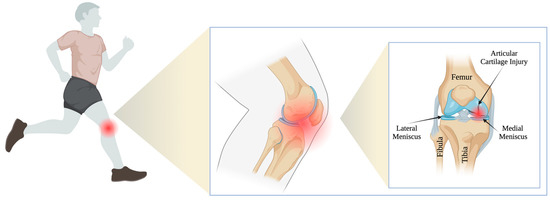

The patients were classified for the procedure according to the ICRS classification. In total, 49 patients, 34 men and 15 women aged 19–38 years (mean = 30 years), underwent cartilage reconstruction surgery. All of these patients were active professional athletes (36 football players, eight basketball players, and five handball players—3 sports disciplines that expose athletes to pivoting/rotational injuries) (Figure 2). Twenty-nine patients presented lesions on the lateral femoral condyle (LFC; 59.2%). The study included patients with a height of 170–185 cm and a weight of 60-70 kg. Twenty patients had lesions on the medial femoral condyle (MFC; 40.8%). Nineteen patients underwent an additional partial or total meniscectomy during surgery. The most common causes of cartilage damage in patients included trauma (65%), osteochondritis dissecans (OCD; 22%), and non-traumatic causes (13%). The mean follow-up time was 19.75 months (SD = 6.79, range = 14–24 months). Table 1 presents information on the patients included in this study.

Figure 2.

A proposed therapeutic approach for articular cartilage injuries in high-performance athletes.